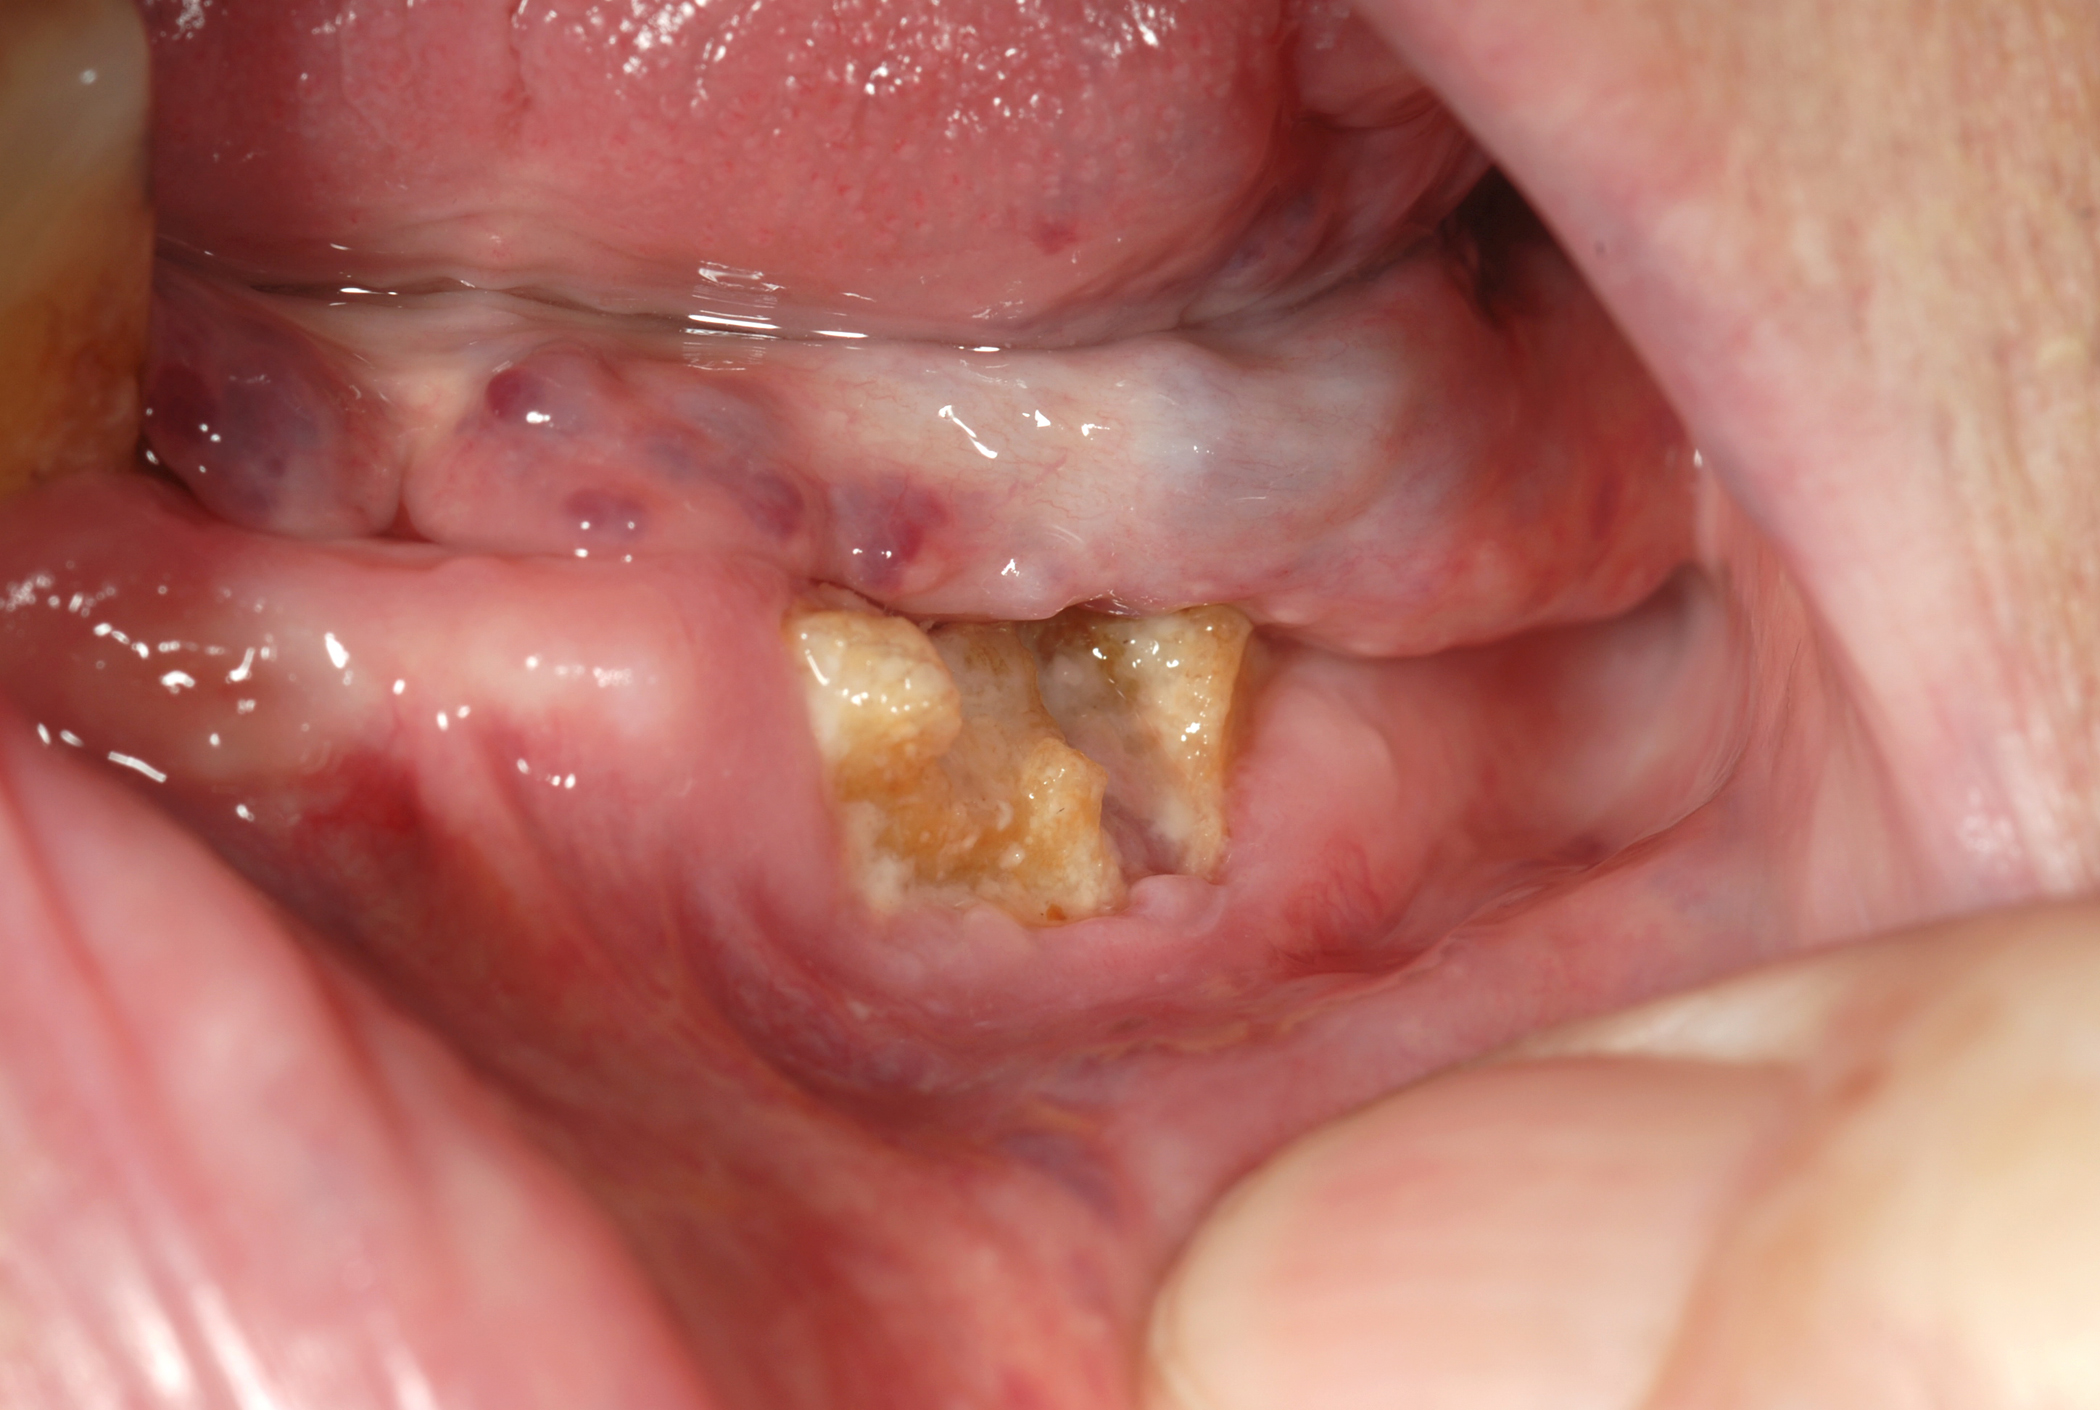

Figure 4 and Figure 5 show examples of MRONJ of the maxilla and mandible, respectively.

A number of drugs can cause medication related osteonecrosis of the jaws (MRONJ). MRONJ is defined by the following criteria:

- presence of exposed bone (or bone that can be probed through an intraoral or extraoral fistula) in the maxillofacial region over a period of 8 weeks;

- stage 1: exposed/necrotic bone in patients who are asymptomatic and have no evidence of infection;

- stage 2: exposed/necrotic bone associated with infection as evidenced by pain and erythema (redness of skin) in the region of the exposed bone, with or without purulent drainage (pus);